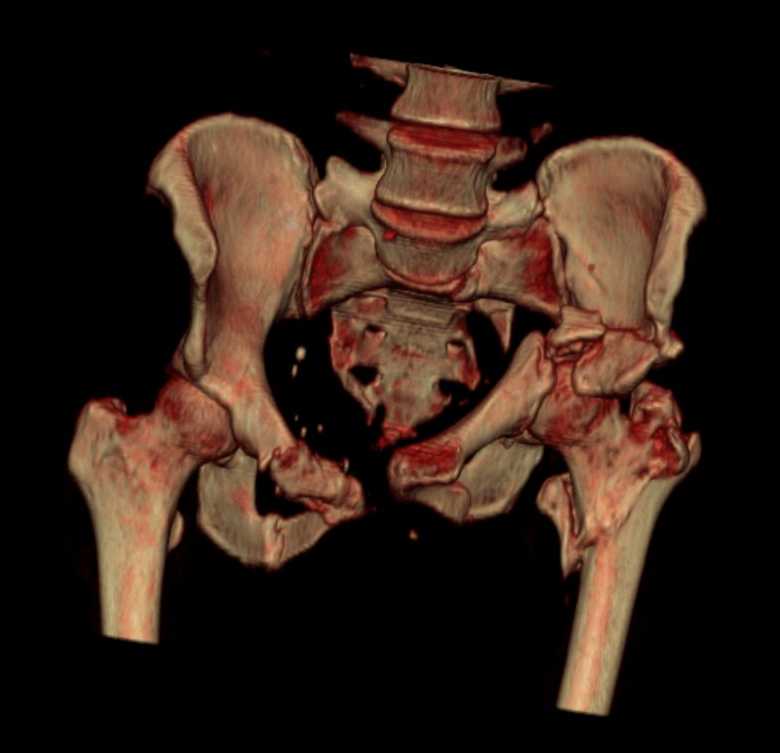

Больная 43 года (промышленный альпинист), 28.07.08 в результате падения с 5 этажа получила политравму: Перелом свода и основания черепа. Вертикально-нестабильное повреждение таза, осложнённое разрывом мочевого пузыря. Чрезвертельный перелом левого бедра. Перелом правой таранной кости, переломовывих правой кубовидной кости. Тупая травма живота, разрыв печени, ушиб почек. Забрюшинная гематома. В день травмы - лапаротомия, ушивание ран печени. Разрыв мочевого пузыря не диагностирован. Течение болезни осложнилось развитием мочевого затёка и обширной пред- и забрюшинной флегмоны, сформировался свищ мочевого пузыря. 19.8.2008 вскрытие, дренировние флегмоны, ревизия мочевого пузыря, обтурация мочевого свища (свищ закрылся в октябре), 1.10.2008 некрэктомия, пластика по Шеде-Лидскому правой кубовидной кости. По результатам КТ диагностирован рак правой почки (диагностическая находка), 8.10.2008 нефрэктомия справа. Переломы велись консервативно. Имеется вертикальное смещение левой половины таза с выраженным отведением крыла (клинически подвижности нет), несросшийся низкий двухколонный перелом левой вертлужной впадины с потерей конгруэнтности, укорочение около5 см, застарелый разрыв лонного сочленения, неправильно сросшиеся переломы обеих ветвей правой лонной кости с укорочением, патологическая подвижность лоно-седалищного фрагмента слева. Правая нижняя конечность неопорна, несмотря на то, что лежа прямую ногу поднимает, ходит на левой ноге (ортопедическая обувь) с костылями, справа тазобедренный ортез. Седалищные нервы работают.Урологи отпустили больную на 6 мес.

Мучаемся мыслями - как все это заставить ходить.Возможно ли первичное протезирование если просто синтезировать лонное сочленение с цементом и ванкомицином? Если делать большую реконструкцию, то с чего начать? Изрубить крыло и заполнить дефекты? Перерубить боковую массу и попытаться развернуть крыло обратно? Ждать год после закрытия свищей?

с большей вероятностью пациентка придет к эндопротезированию тазобедренного сустава, поэтому необходимо создать надежную "опору" сзади и подготовить бедро к имплантации любой классической ножки.ИМО бедренной кости GN, АНФ на таз,по необходимости остеотомия крестца, восстановление конфигурации задних отделов и устранение вертикального смещения половины таза. дождаться сращения крестца и бедренной кости. второй этап эндопротезирование: ножка цвай-мюллер или спаторно,ацетабулярно онкологическое антипротрузионное кольцо левое либо ацетабулярный компонент по индивидуальным параметрам для протезирования после резекции лонной седалищной костей и вертлужной впадины при онкопатологии. в кольцо пару трения металл\металл с цементной чашкой IMPLANTCAST, т.к. пациентка молодая.лонные кости можно оставить в покое, какой никакой рубец есть. с уважением Сергей.